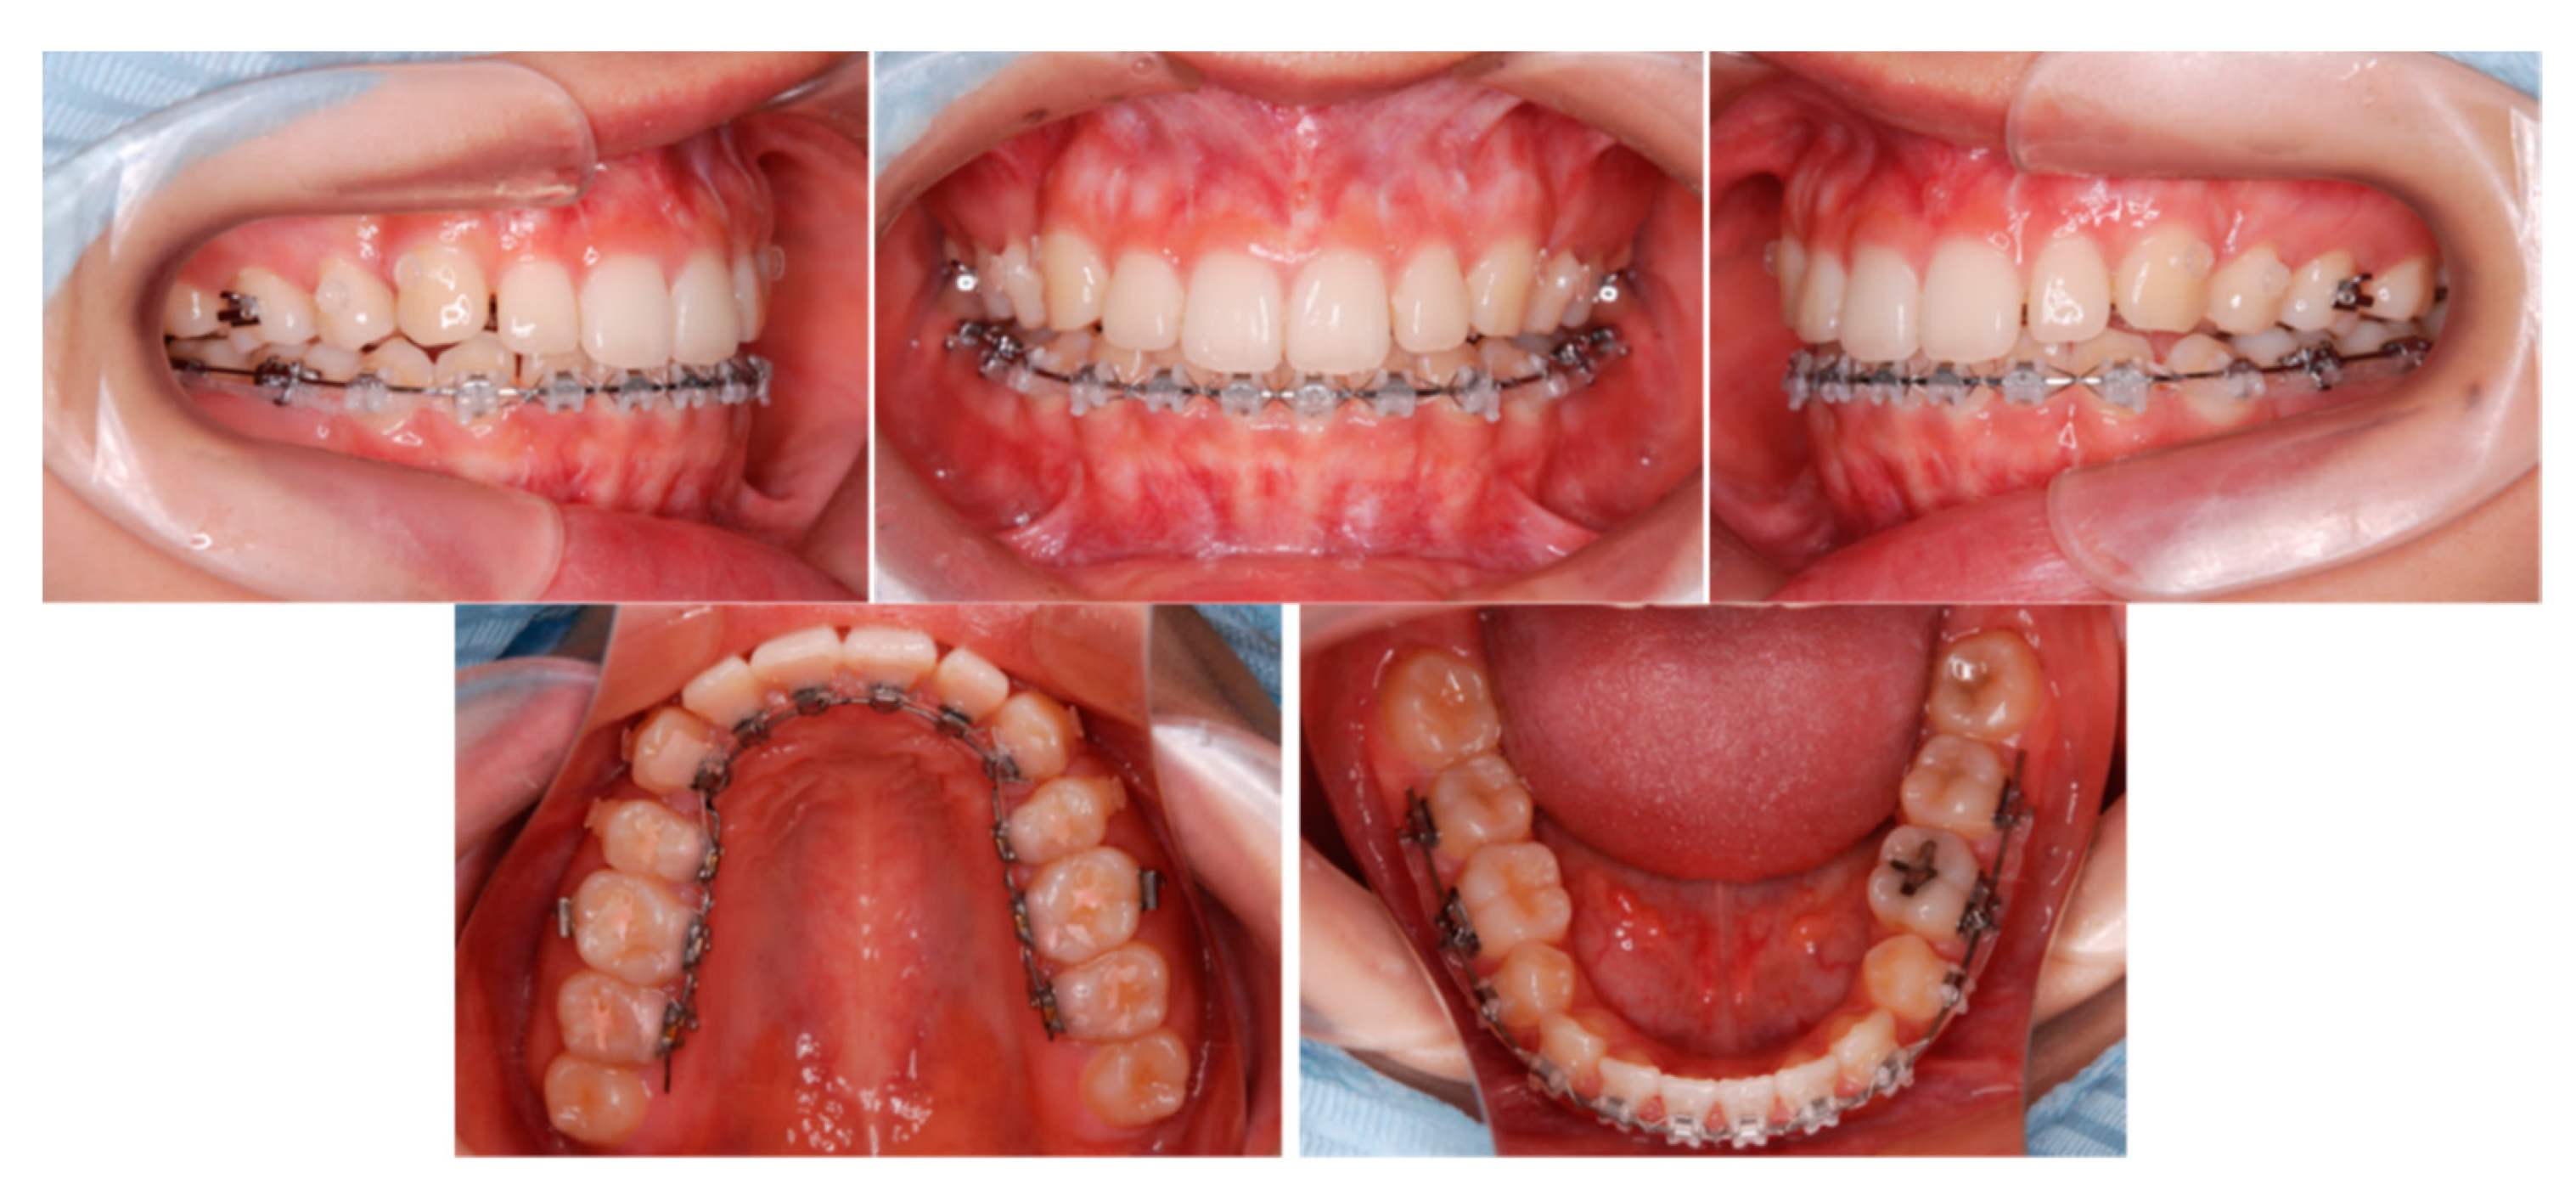

6.5. Treatment Results